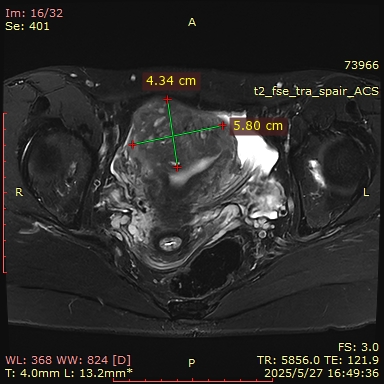

MRI(2025-05-27):子宫肌层增厚,其内信号欠均匀,肌层内见一等类圆形T2WI低信号,其内可见T1WI高信号,大小约为40mm*39mm。左侧附件区可见类圆形短T2异常信号影,大小约为8mm*5mm;右侧附件形态、大小、信号未见明显异常。盆腔少量积液。